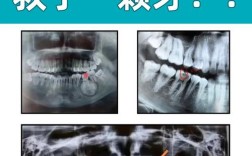

牙周炎的影像学检查是诊断、评估疾病严重程度、制定治疗计划以及监测治疗效果的重要手段,它主要目的是观察牙槽骨的吸收情况,因为牙槽骨破坏是牙周炎的特征性表现,以下是牙周炎常用的影像检查方法,按常用程度和适用性排序:根尖片(牙片)原理:将X光胶...